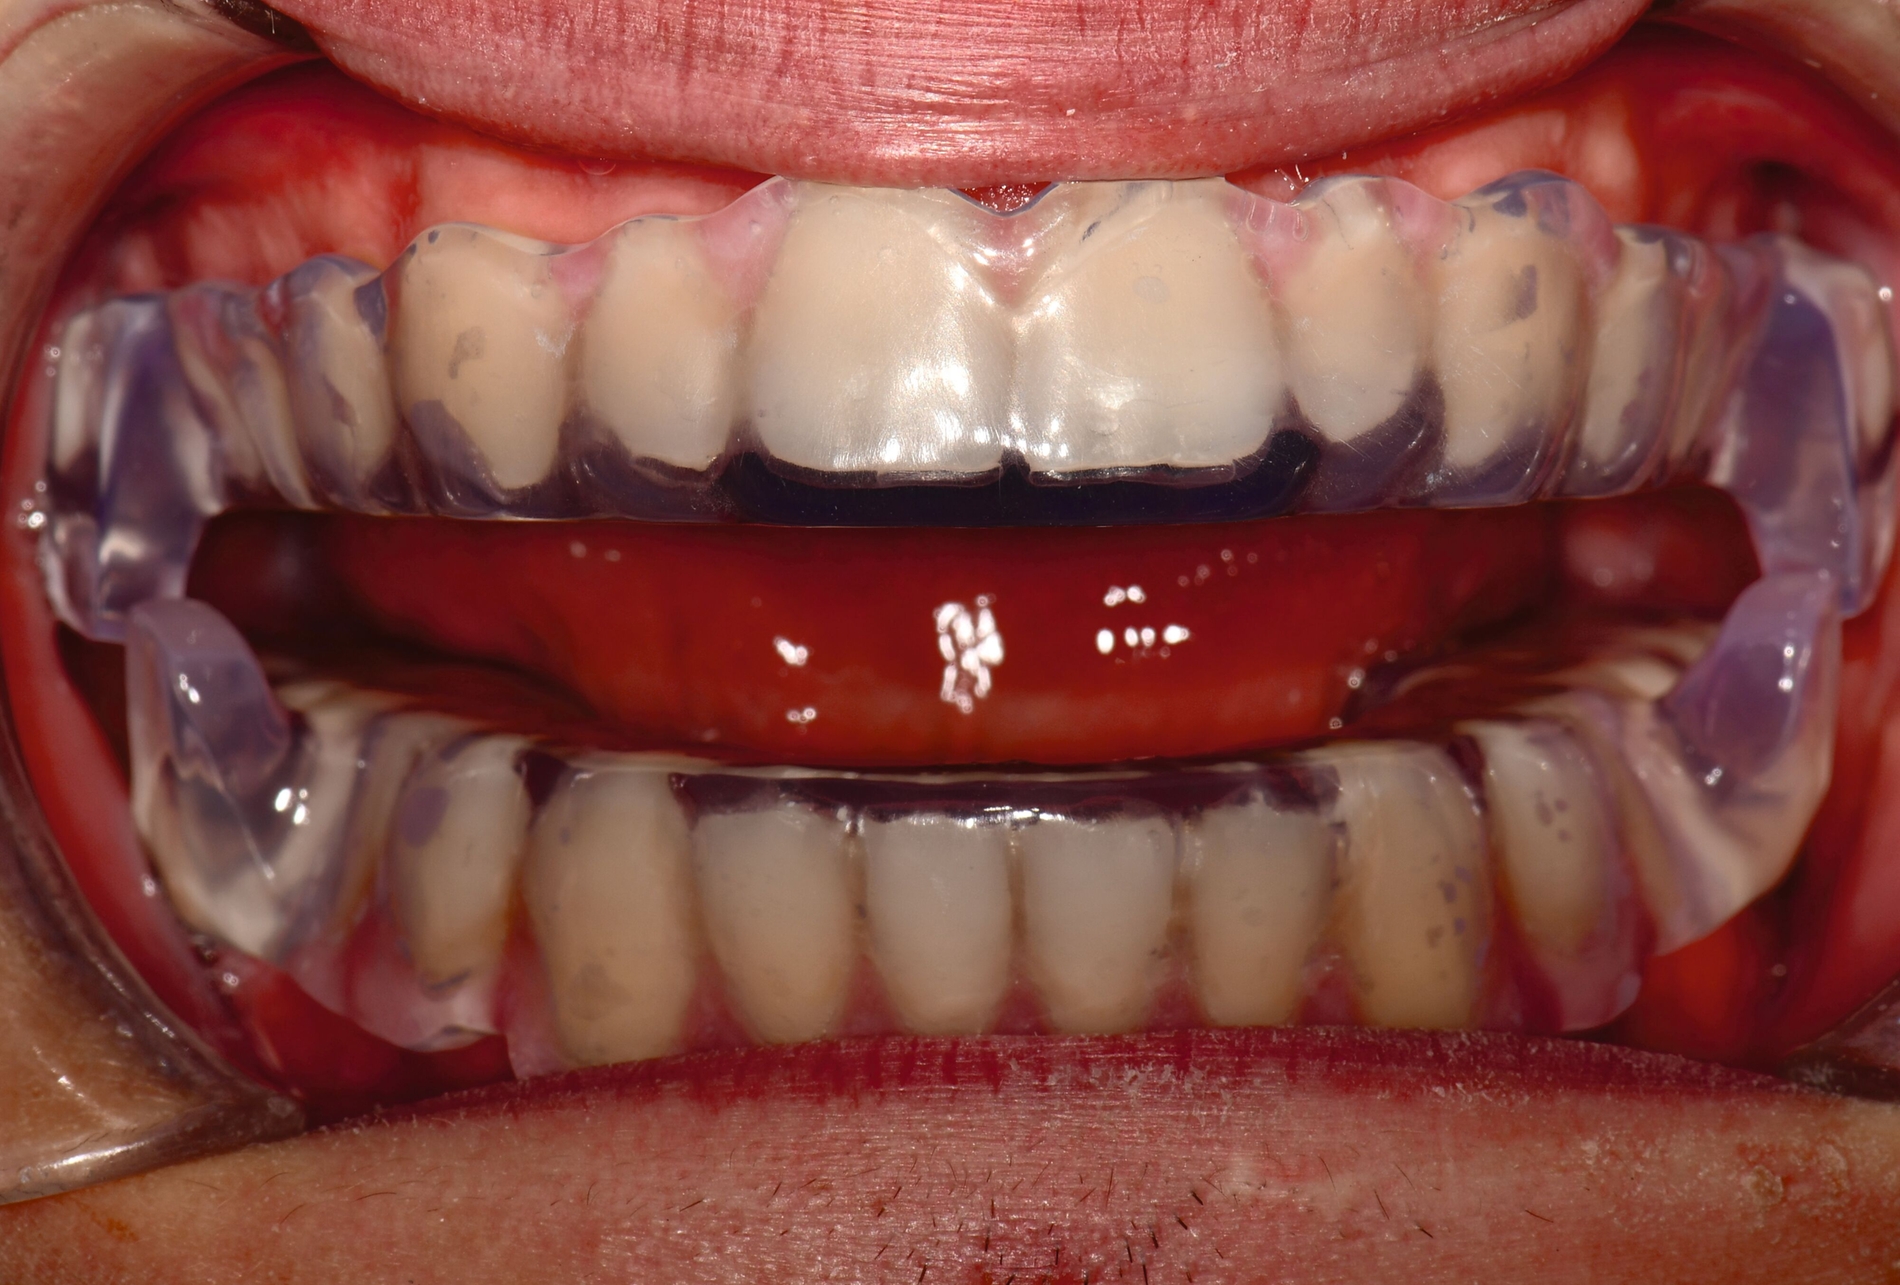

Herausnehmbare Apparaturen

Als hochinnovatives Feld hat sich auch die Herstellung herausnehmbarer Apparaturen im 3-D-Druck entwickelt (Abbildung 4), beschränkt sich jedoch noch auf einzelne Forschungsansätze [Al Mortadi et al., 2012; van der Meer et al., 2016; Graf et al., 2022; Keller et al., 2022]. Intensiv an neuen Konzepten in der Herstellung 3-D-gedruckter herausnehmbarer Apparaturen wird am Universitätsklinikum Heidelberg geforscht. Da herausnehmbare kieferorthopädische Apparaturen im Regelfall bei jungen Patienten eingesetzt werden, kommt dem Vorteil einer unbegrenzten Replikation und einer kostengünstigen und schnelleren Herstellung ein besonderer Stellenwert zu.

Im Unterschied zu konventionellen Apparaturen bestehen die 3-D-gedruckten Apparaturen vollkommen aus Kunststoff. Eine Einarbeitung metallischer Elemente nach dem 3-D-Druck ist möglich [Al Mortadi et al., 2012; Al Mortadi et al., 2024], erfordert jedoch zusätzlichen Zeitaufwand. Zur Herstellung herausnehmbarer Apparaturen eignen sich konventionelle praxisinterne 3-D-Stereolithografie-Drucker, die in vielen Fällen bereits im regulären Praxisalltag zum Modelldruck verwendet werden. Die verwendeten Kunststoffe sollten dabei eine Klasse-IIa-Zertifizierung aufweisen, so dass ein sicherer langfristiger intraoraler Einsatz der Apparatur gewährleistet ist. Weiter muss die Apparatur nach dem 3-D-Druck gemäß den Herstellerangaben nachprozessiert werden. Im Regelfall beinhaltet dieser Prozess ein Waschen in Isopropylalkohol (IPA) sowie eine Nachhärtung im Lichthärtegerät. Eigens durchgeführte Studien sowie die bisherige klinische Erfahrung bestätigen eine hohe mechanische Stabilität, eine hohe Passgenauigkeit sowie eine breite Akzeptanz der Patienten [Roser et al., 2021; Roser et al., 2023; Segnini et al., 2023]. Des Weiteren wecken die 3-D-gedruckten Apparaturen bei den meist jungen Patienten großes Interesse, was wiederum die Trage-Compliance unterstützt. Durch weitere Entwicklungen im 3-D-Druckbereich wird zukünftig auch ein Farbdruck möglich werden.